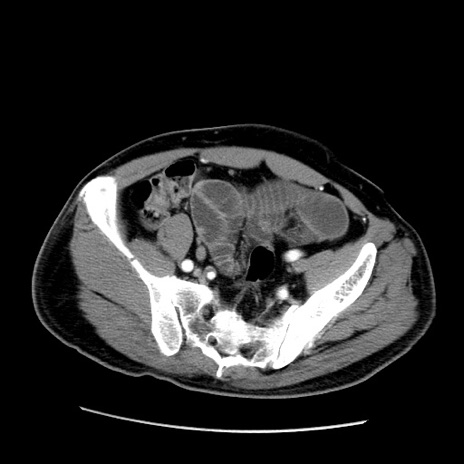

症例22(横断像)

【症例】50歳代男性

【主訴】腹痛

【現病歴】AVMからの被殻出血のため回復期リハ病棟入院中。 本日午後3時頃急に下腹部痛が出現した。

【既往歴】AVM、被殻出血、虫垂炎、高血圧

【身体所見】意識晴明、左半身不全麻痺、会話の理解は良好、36.5°C、腹部:膨隆、全体に板状硬、下腹部正中に圧痛点あり、反跳痛-、筋性防御不明、右下腹部にope scar

【データ】WBC 9400、CRP 0.06